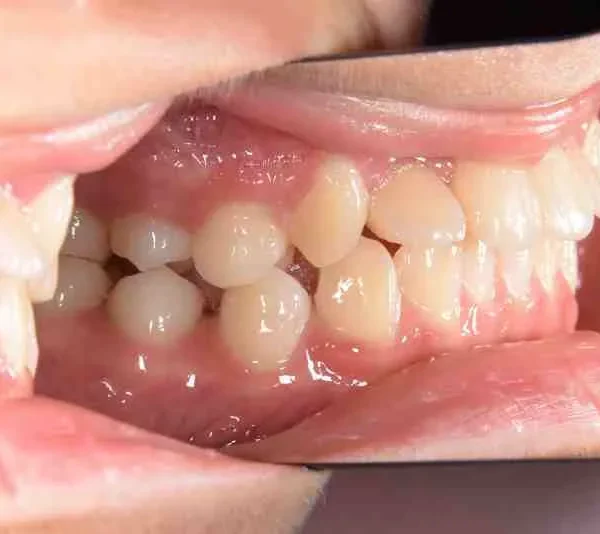

• 治療終了後

治療終了後

マルチブラケット装置は使わずに、最低限の必要な装置を使って目立たないように治療しました。

治療回数29回、2年10ヶ月の治療期間で矯正治療を終了しました。

主訴が改善され、ご満足頂きました。